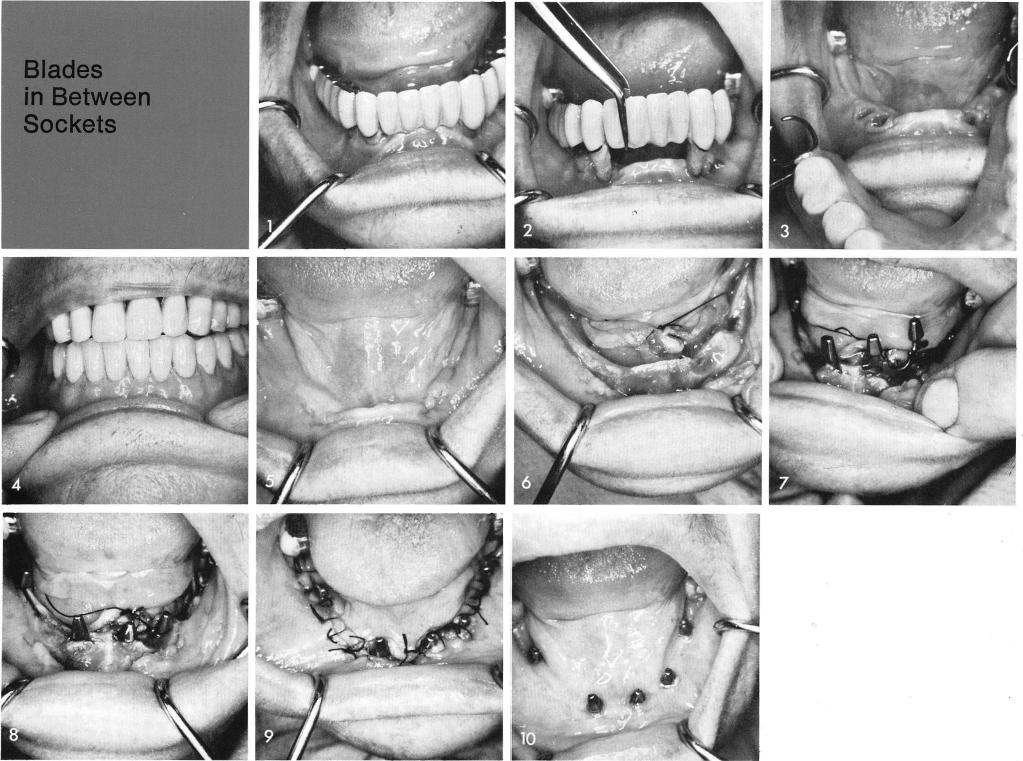

In this particular case the loose teeth were able to be removed from their sockets by merely pulling out the original prosthesis, figs. 1, 2. An immediate removable partial denture was constructed until three months passed by for complete bony fill in of the sockets, figs. 3, 4. After three months went by, fig. 5, the tissues were incised and reflected, fig. 6, and blades were inserted in between the remaining sockets and directly into some of the sockets as seen by the socket blade in the left cuspid area, figs. 7, 8. The tissues were sutured closed, fig. 9. Two weeks later the tissues were completely healed, fig. 10. A specially designed full arch fixed prosthesis was processed. Being that so much vertical bone loss took place a false gum line had to be included in the design, fig. 11. This gum line, however, ended exactly where a natural crown would usually end at the gingival margins of the blade posts. The bridge was then cemented permanently into position, figs. 12, 13, 14, 15. A post-operative x-ray of this case, fig. 16.

1 Immediate removable partial denture placed in mandible